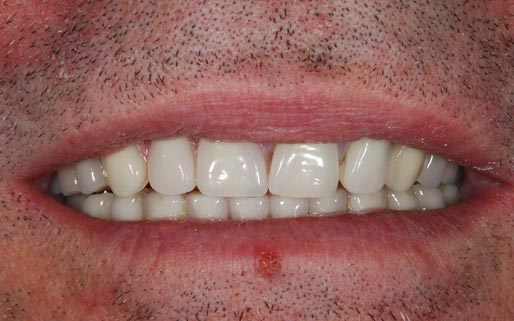

Faccette estetiche in ceramica